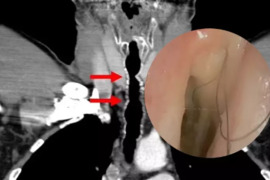

21-dən az dişi olan insanlarda piylənmə riski artır. xəbər verir ki, bunu "Gerodontology " jurnalında dərc olunan araşdırma göstərib. Alimlər 65-89 yaş arası 1765 nəfərin tibbi qeydlərindən alınan məlumatları təhlil ediblər. İştirakçıların təxminən 73%-i artıq çəki və ya obez olub. Hər itirilə